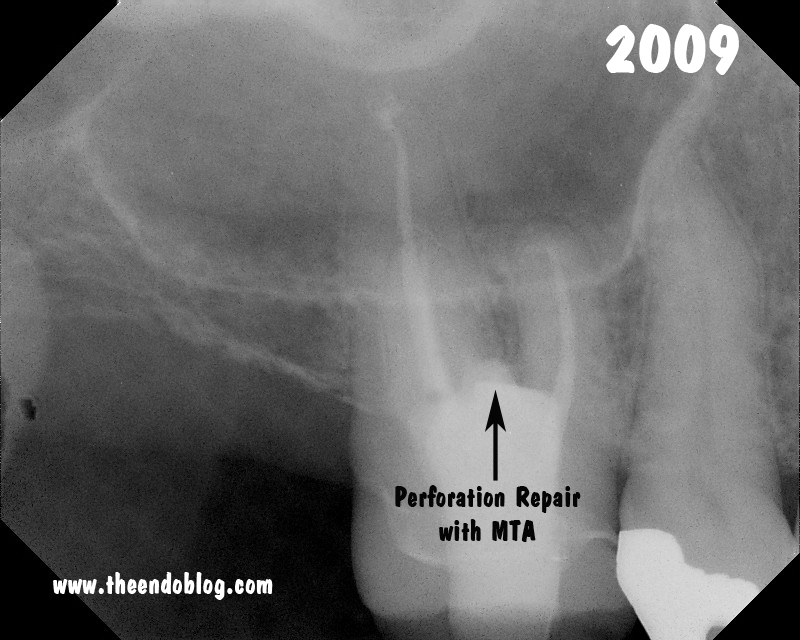

The treatment for this tooth was RCT completion and repair of the iatrogenic damage using Mineral Trioxide Aggregate (MTA).

Fortunately,

with good repair materials, the prognosis for a tooth like this is

still good. A 7 year recall finds the tooth in full function and

asymptomatic.